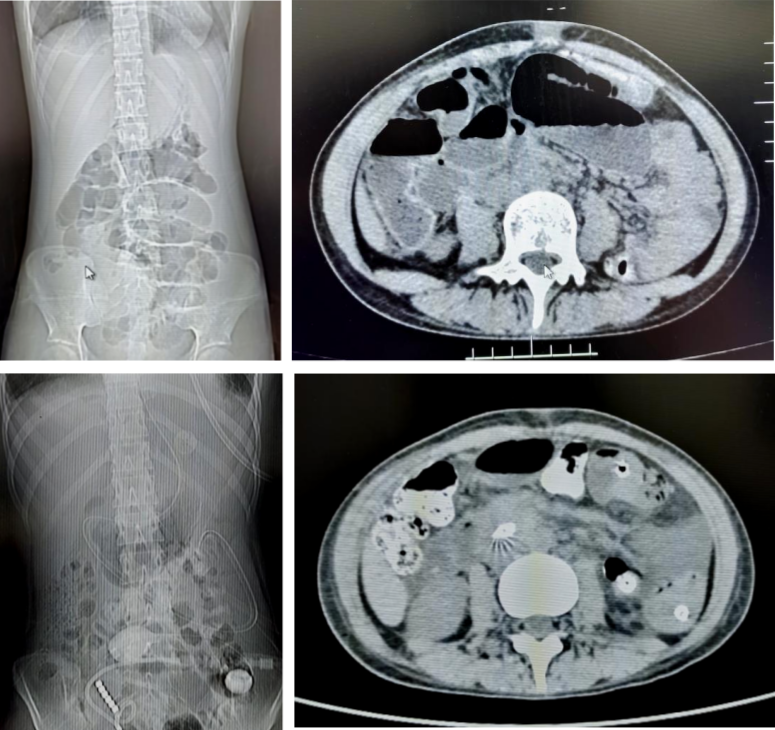

病例2

18岁的患者叶女士,因行阑尾穿孔导致盆腔脓肿后出现肠梗阻。后在我院放射介入室行DSA引导下经鼻肠梗阻导管置入术,术后当日患者腹胀较前明显缓解,术后第3天患者排气、排便,肠管恢复通畅,拔除肠梗阻导管。